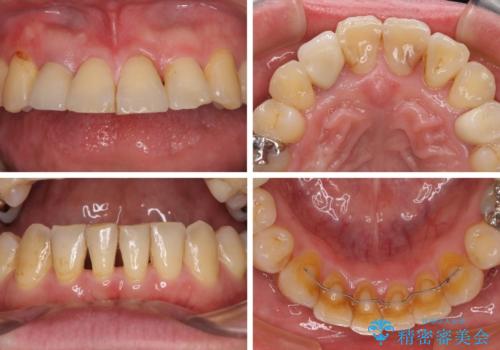

咬み合わせは受け口傾向であり、上顎前歯の叢生が顕著であったことから、第1小臼歯抜歯による矯正治療も検討しましたが、下顎大臼歯を左右ともに抜歯するため、非抜歯による矯正治療を行うこととしました。

矯正治療でインプラント埋入を行い、矯正治療後に気になる前歯と合わせてオールセラミッククラウンによる補綴治療を行うこととしました。

骨造成や歯肉移植など、治癒期間の長い処置を必要としたため治療期間は長くなりましたが、安定した咬み合わせと整った歯列となり、患者様には大変満足していただきました。